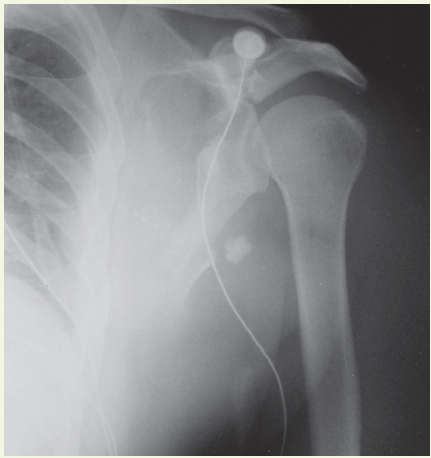

A 56-year-old man, who was involved in an automobile accident, was brought to the emergency department by ambulance. He was awake, intoxicated with alcohol, and complained particularly of pain in his left shoulder. The patient was unable to recall any details of the accident; he believed that he had been hospitalized for a back spasm. Because of the patient’s discomfort, physical examination of his left shoulder was limited.

Laboratory testing. Muscular or ligamentous injury was initially suspected, and a roentgenogram of the shoulder was obtained. The film revealed a comminuted fracture of the left scapula that involved the neck, body, and spine. The glenohumeral relationship was maintained. Also visualized was a fracture of the posterolateral aspect of the fourth through eighth ribs, an injury which can increase the risk of a tension pneumothorax, hemothorax, or pulmonary and visceral injury.

Discussion. The physician noted that a scapular fracture may occur from direct violence, sudden contraction of divergent muscles, or electric shock. Fractures to the body of the scapula, which usually result from high-energy trauma, are associated with the greatest morbidity. A plain x-ray film is diagnostic; a CT scan can detect involvement of the glenoid fossa.